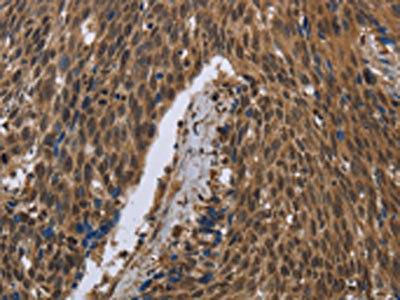

The image on the left is immunohistochemistry of paraffin-embedded Human breast cancer tissue using CSB-PA697513(PIP Antibody) at dilution 1/50, on the right is treated with fusion protein. (Original magnification: ×200)

The image on the left is immunohistochemistry of paraffin-embedded Human cervical cancer tissue using CSB-PA697513(PIP Antibody) at dilution 1/50, on the right is treated with fusion protein. (Original magnification: ×200)